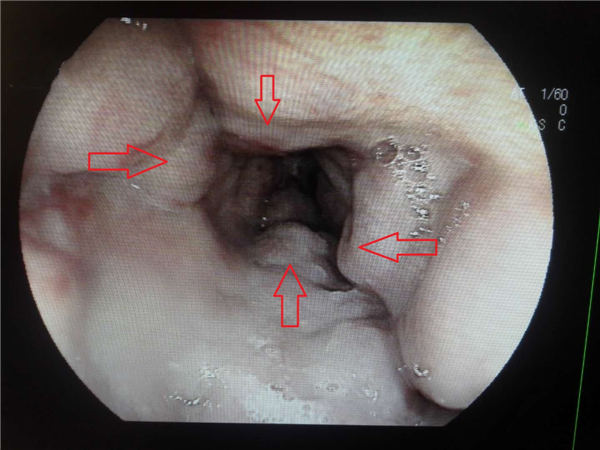

胃镜检查显示:食管多条静脉曲张(下图红箭头所示),胃底静脉曲张伴糜烂渗血(下图绿箭头所示)